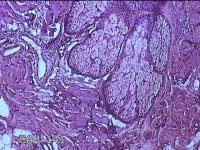

头部肿物

性别

男

年龄

21岁

临床诊断

头皮肿物

一般病史

发现头部结节10余年,无明显疼痛及不适。

标本名称

头部结节

大体所见

灰白暗红色带皮肤样结节1.5x1.3x0.3cm一个,切开结节呈实性,切面灰白粉红色,质软。